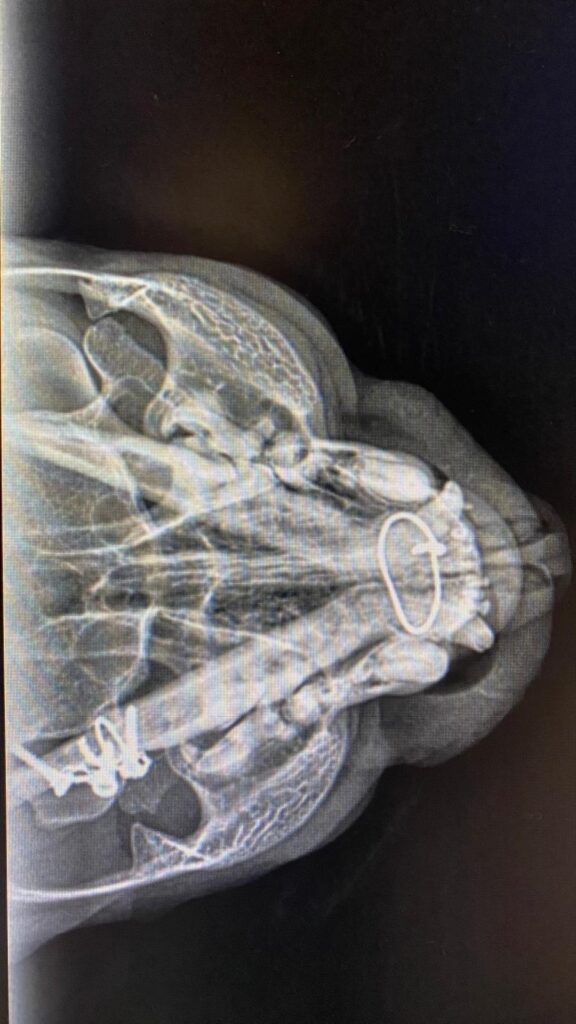

Dann der Schreck für Alle auf dem Röntgenbild:

Hubsis Unterkiefer ist wohl nach einem Bruch in der Vergangenheit verdrahtet worden, die Drähte und Schrauben sind deutlich zu erkennen! ![]()

Eine Drahtschlinge reicht bis an sein Kinn.

Es wird nun angenommen, dass diese Schlinge Hubsis Körper massiv ärgert und stört und deshalb auch diese Beule entstanden ist.